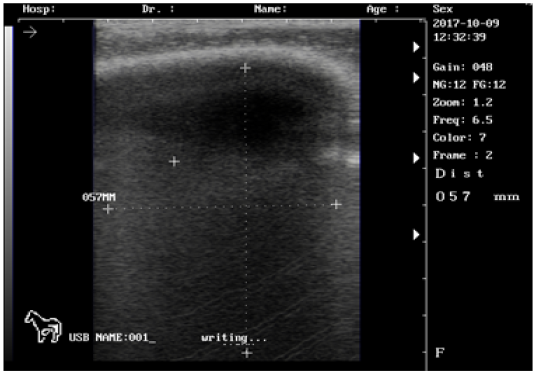

Ultrasound images of the testis of 7 months lamb showing: high echogenicity of the testicular parenchyma; mediastinum testicular diffusly echogenic